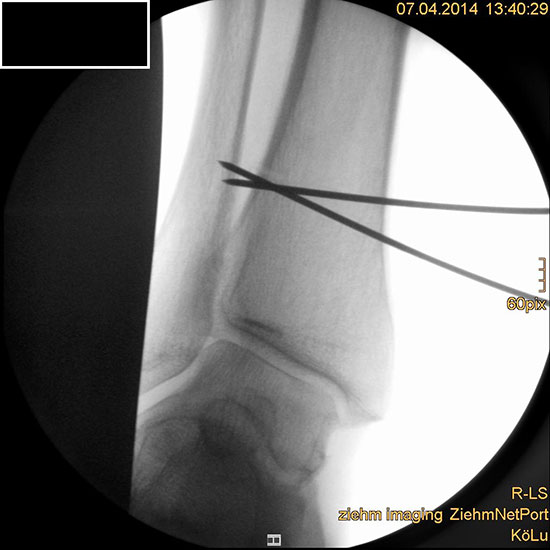

Auch hier wird die Korrektur im CORA (Center oft Rotation and Angulation) durchgeführt. Primär werden intraoperativ unter Bildwandler Kontrolle Kirschner Drähte als Sägelehre konvergierend eingebracht. Dann wird der geplante medialbasige Keil mit der oszillierenden Säge entfernt. Die laterale Kortikalis sollte geschont werden, sie dient als Drehpunkt für die Osteotomie. Die Osteosynthese kann dann im Sinne einer Zuggurtung ein besonders stabiles Konstrukt bilden. Liegen mehrdimensionale Deformitäten vor, die eine Korrektur in Translations- und Rotationsebene erfordern, ist eine Durchtrennung der lateralen Kortikalis notwendig, ebenso bei ausgedehnten Korrekturen mit Keilhöhen über 10mm 218.

Wir benutzen zur Osteosynthese 3,5 mm LCP T-Platten. In der intraoperativen Röntgenkontrolle kann im seitlichen Bild die Zentrierung des Talus überprüft werden, und ggf. durch eine milde extendierende oder flektierende Korrekturkomponente verbessert werden 18. Eine begleitende Deformität der Fibula korrigieren wir üblicherweise mit einer z-förmigen Osteotomie die wir mit einem 1/3 Rohrplättchen sowie einer Zugschraube sichern 18.